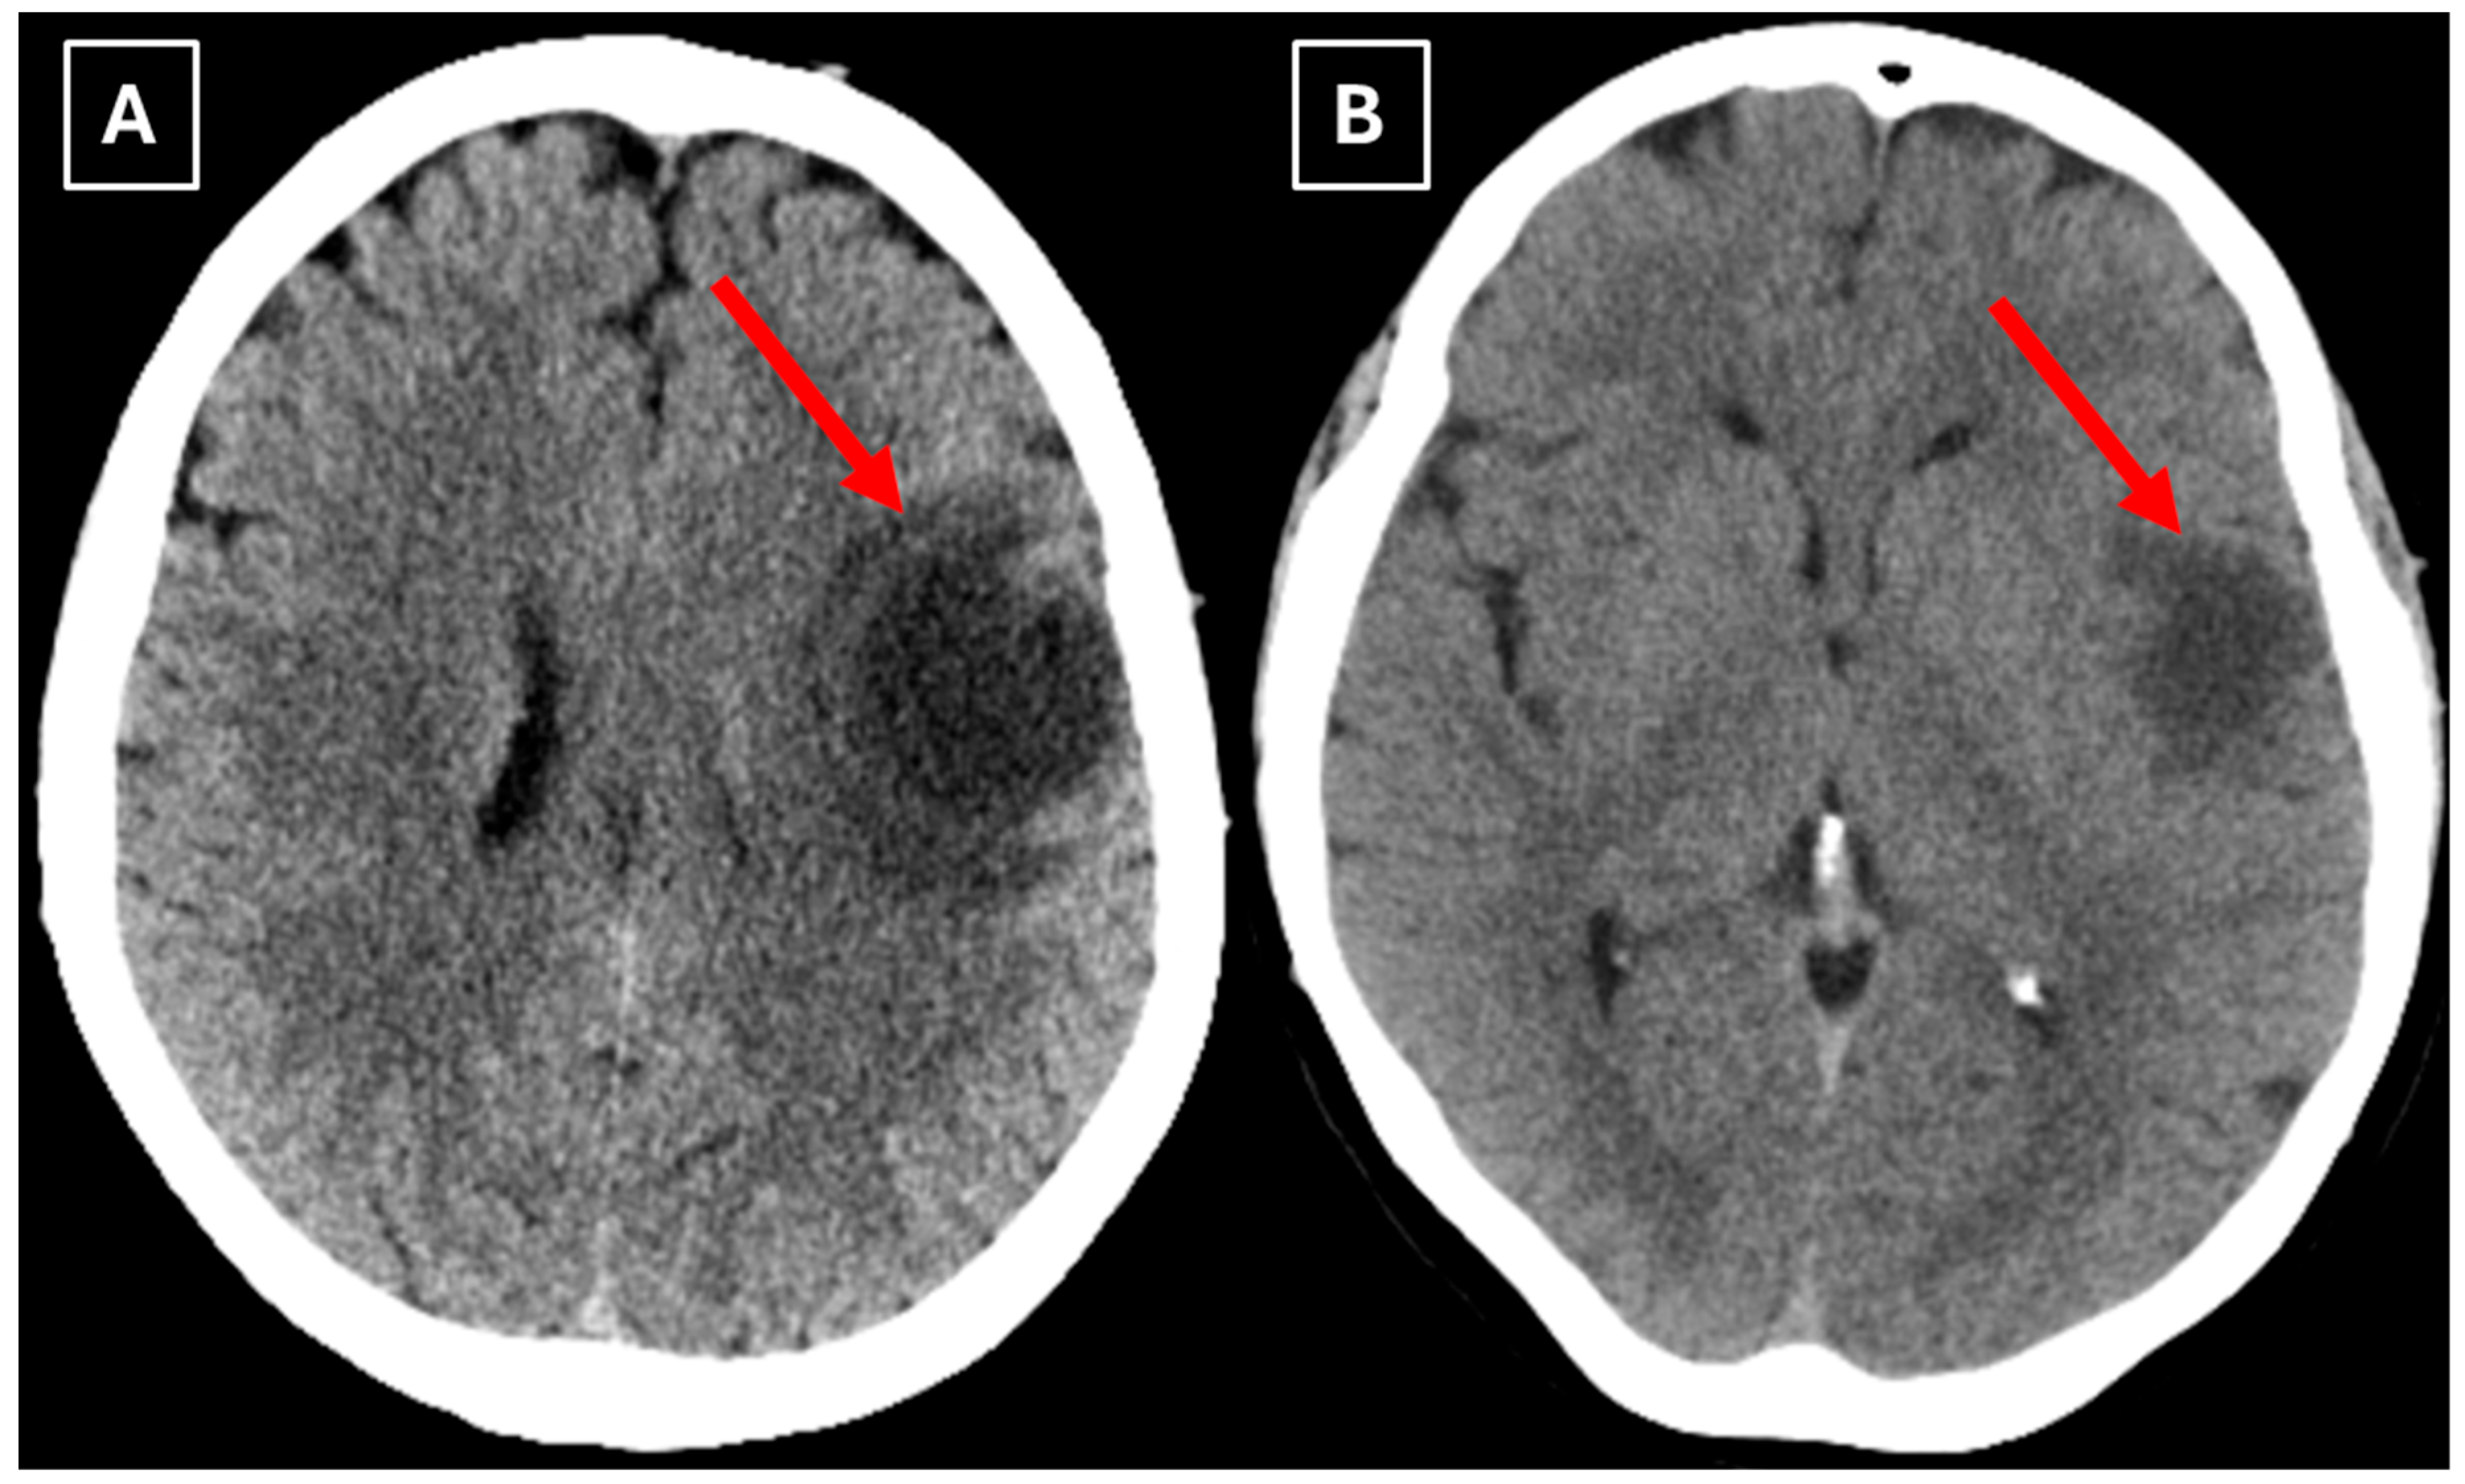

A computed tomography (CT) scan of the brain revealed a 3.5 cm hypodense lesion in the left frontal lobe with mild perifocal edema (Figure 1). Due to the unclear nature of the lesion, additional examinations were performed to rule out oncopathology, including mammography and breast ultrasound, as well as chest and abdominal CT scans, all of which were negative for oncological findings.

Figure 1. Native head CT without I/V contrast Images (A,B) show a. Hypodense lesion in the left hemisphere, basal parts of the frontal lobe. Measuring up to at least 3.5 cm in maximum size, with mild perifocal edema. Red arrow—indistinct formation.

We also found similarities between this case and the classical imaging features of TDLs described in the literature. Hypoattenuation on noncontrast CT corresponding to enhancing areas on MRI is another useful imaging finding in TDLs [10], which may be explained by the tissue rarefaction caused by the active demyelination rather than increased cellularity, which is seen in tumors, thereby supporting the use of MRI with noncontrast CT in TDL diagnosis. Furthermore, restricted diffusion along the lesion margin with elevated central ADC values, in contrast to neoplasms which more commonly show central diffusion restriction, have been described as a commonly presenting feature of TDLs [3,4,10], which was also observed in this case (Figure 5A,B).